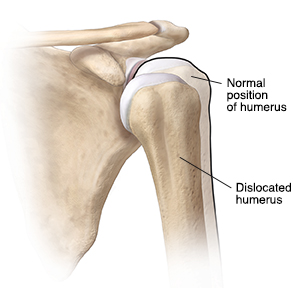

If you have dislocated your shoulder, your upper arm bone (humerus) has moved out of your shoulder joint. This is the most frequently dislocated major joint of your body. Dislocation is often caused by a major force that separates your shoulder joint's ball (the top rounded part of your upper arm bone) from your joint's socket (glenoid).

Your shoulder can be either partly or fully dislocated. Partial dislocation is when the head of your upper arm is partly out of your shoulder socket. Complete dislocation is when the head of your upper arm is completely out of your shoulder socket.

Your shoulder can dislocate forward and downward, or backward. It can be partly or fully dislocated.